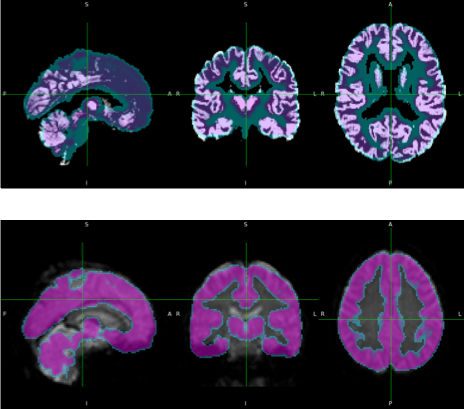

Structural MRI is a non-invasive imaging technique that provides detailed visualization of brain anatomy and detect structural lesions or abnormalities. It characterizes brain structure, focusing on detecting associated structural abnormalities like tumors, stroke, or degenerative changes, but does not directly assess functional dynamics. It serves as an anatomical reference for other functional and advanced techniques like fMRI and DTI. This is crucial for diagnosing neurological disorders, tracking disease progression, and understanding the impact of various conditions on brain structure.

Image processing and analyses are predominantly conducted using MATLAB and Python. External plugins, including SPM25 and CAT12, facilitate the preprocessing of sMRI, fMRI, and PET images. The preprocessing pipeline encompasses segmentation, slice timing correction, motion correction, coregistration, normalization, and smoothing. FSL, a Python-based library, assists in the preprocessing and analysis of dMRI and fMRI. Additionally, MRIcron is employed for image visualization and comparison.

Statistical analyses are employed to compare group differences. Structural differences are assessed using voxel-based morphometry, surface-based morphometry, and deformation-based morphometry. Functional differences are measured through seed-based correlation analysis and independent component analysis. Diffusion tract measurements are compared via tract-based spatial statistics and voxelwise statistics. PET images are analyzed using standard uptake value measurements.

In this stage, images are processed for motion correction, denoising, smoothing, modulation, and alignment between modalities

Structural MRI